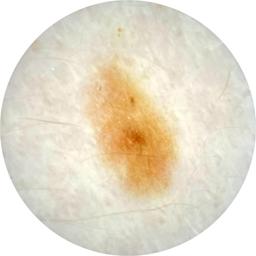

ISIC_4698082

Clinical

Field Value

acquisition_day 92

age_approx 35

anatom_site_1 Trunk

anatom_site_2 Posterior trunk

anatom_site_general posterior torso

concomitant_biopsy False

diagnosis_1 Benign

diagnosis_confirm_type single image expert consensus

family_hx_mm False

fitzpatrick_skin_type I

image_manipulation instrument only

image_type dermoscopic

lesion_id IL_0295269

patient_id IP_6143425

personal_hx_mm True

sex female